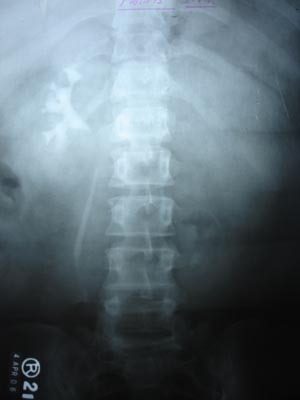

Single Kidney

IVP showing single kidney: This is a case of single kidney.congenital absent of other kidney Confirmed by USG & CT abdomen.